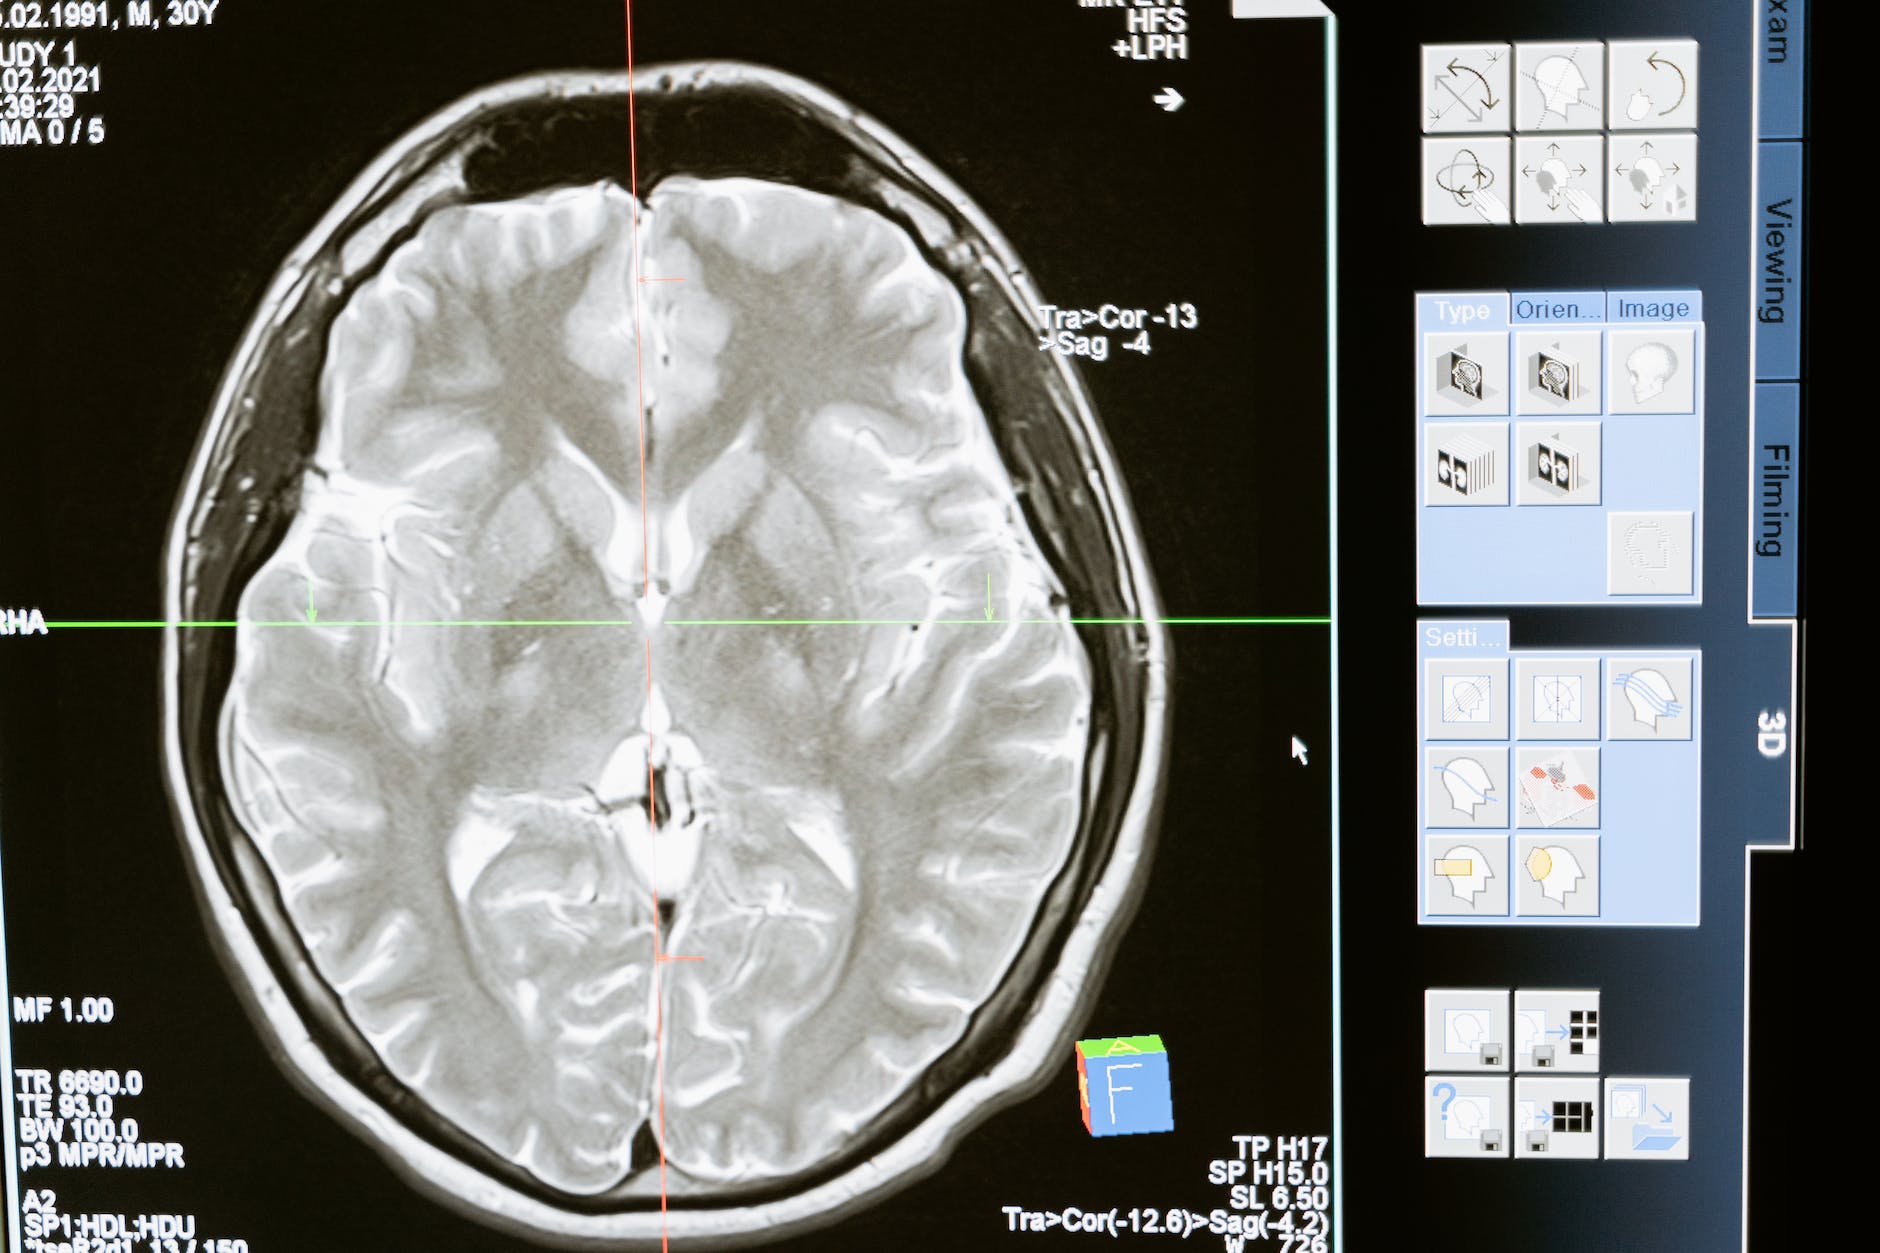

Recent advances in neuroimaging, such as fMRI and EEG, have provided insight into how the brain functions during hypnosis. These studies reveal distinct patterns of brain activity, including changes in connectivity between various regions of the brain that are involved in attention, consciousness, and control. Specifically:

- Altered Connectivity: During hypnosis, increased connectivity between the dorsolateral prefrontal cortex (responsible for executive functions and planning) and the insula (associated with bodily awareness) has been observed. This may explain the heightened focus and altered perception of physical sensations, such as pain.

- Decreased Activity in the Default Mode Network (DMN): The DMN is associated with self-referential thinking and mind-wandering. Hypnosis tends to reduce activity in this network, contributing to a deep state of focused attention and dissociation from the external world.

- Pain Modulation: Studies indicate that hypnosis can reduce pain perception by altering activity in areas like the anterior cingulate cortex and somatosensory cortex. These changes are particularly relevant for clinical applications like pain management.

• Harvard Medical School Study (2016): Research from the Department of Psychiatry at Harvard utilized functional MRI (fMRI) to study brain activity in individuals under hypnosis. They found that hypnosis led to decreased activity in the dorsal anterior cingulate cortex, which is involved in cognitive control and self-consciousness. Simultaneously, the connection between the dorsolateral prefrontal cortex and the insula was strengthened, which may explain how hypnosis enables individuals to exert control over bodily sensations and pain. Hypnotherapists can leverage this enhanced mind-body connection to manage chronic pain conditions. For example, during hypnosis, clients can be guided to direct attention away from pain or use visualization techniques to alter their perception of it. This is particularly effective for conditions like fibromyalgia, where traditional medical interventions may be limited.• Stanford University Study (2012): Research led by Dr. David Spiegel at Stanford found that individuals highly susceptible to hypnosis showed changes in brain areas associated with executive function, emotional regulation, and somatic awareness. The study used EEG to monitor brain waves and found that highly hypnotizable subjects exhibited more theta wave activity, typically associated with deep relaxation and altered states of consciousness.